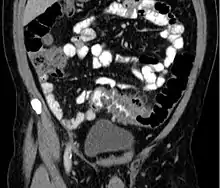

People with the above symptoms are commonly studied with computed tomography, or a CT scan.[29] Ultrasound can provide preliminary investigation for diverticulitis. Amongst the findings that can be seen on ultrasound is non-compressing outpouching of bowel wall, hypoechoic and thickened wall, or there is obstructive fecalith at the bowel wall. Besides, bowel wall oedema with adjacent hyperechoic mesentery can also be seen on ultrasound. However, CT scan is the mainstay of diagnosing diverticulitis and its complications.[14] The diagnosis of acute diverticulitis is made confidently when the involved segment contains diverticula.[30] CT images reveal localized colon wall thickening, with inflammation extending into the fat surrounding the colon.[31] Amongst the complications that can be seen on CT scan are: abscesses, perforation, pylephlebitis, intestinal obstruction, bleeding, and fistula.[14]